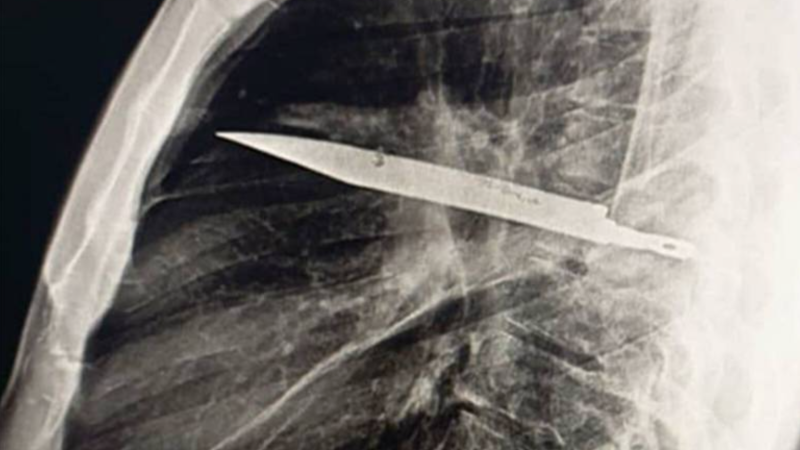

Topolánek otevřeně o rakovině: Mám šanci žít déle než pět let. Popsal i náročnou operaci

Bývalý premiér Mirek Topolánek otevřeně promluvil o svém boji s rakovinou slinivky. V rozhovoru pro DVTV popsal náročnou operaci a svůj režim. Věří, že má...

Topolánek otevřeně o rakovině: Jsem unavenější. Upozornil na absenci screeningu